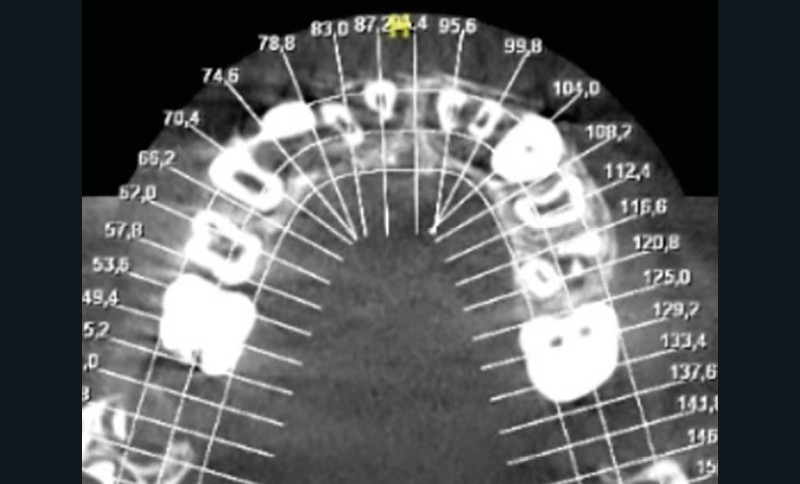

Faute de suivi, aucune prise en charge endodontique n’avait été entreprise dans les jours suivant le traumatisme. Du fait de la mobilité importante des incisives maxillaires, la contention a été laissée en place. Une radiographie panoramique et un cone beam ont également été réalisés. Ces derniers montrent une résorption radiculaire externe des dents 12-11-21-22 (fig. 1a-c).